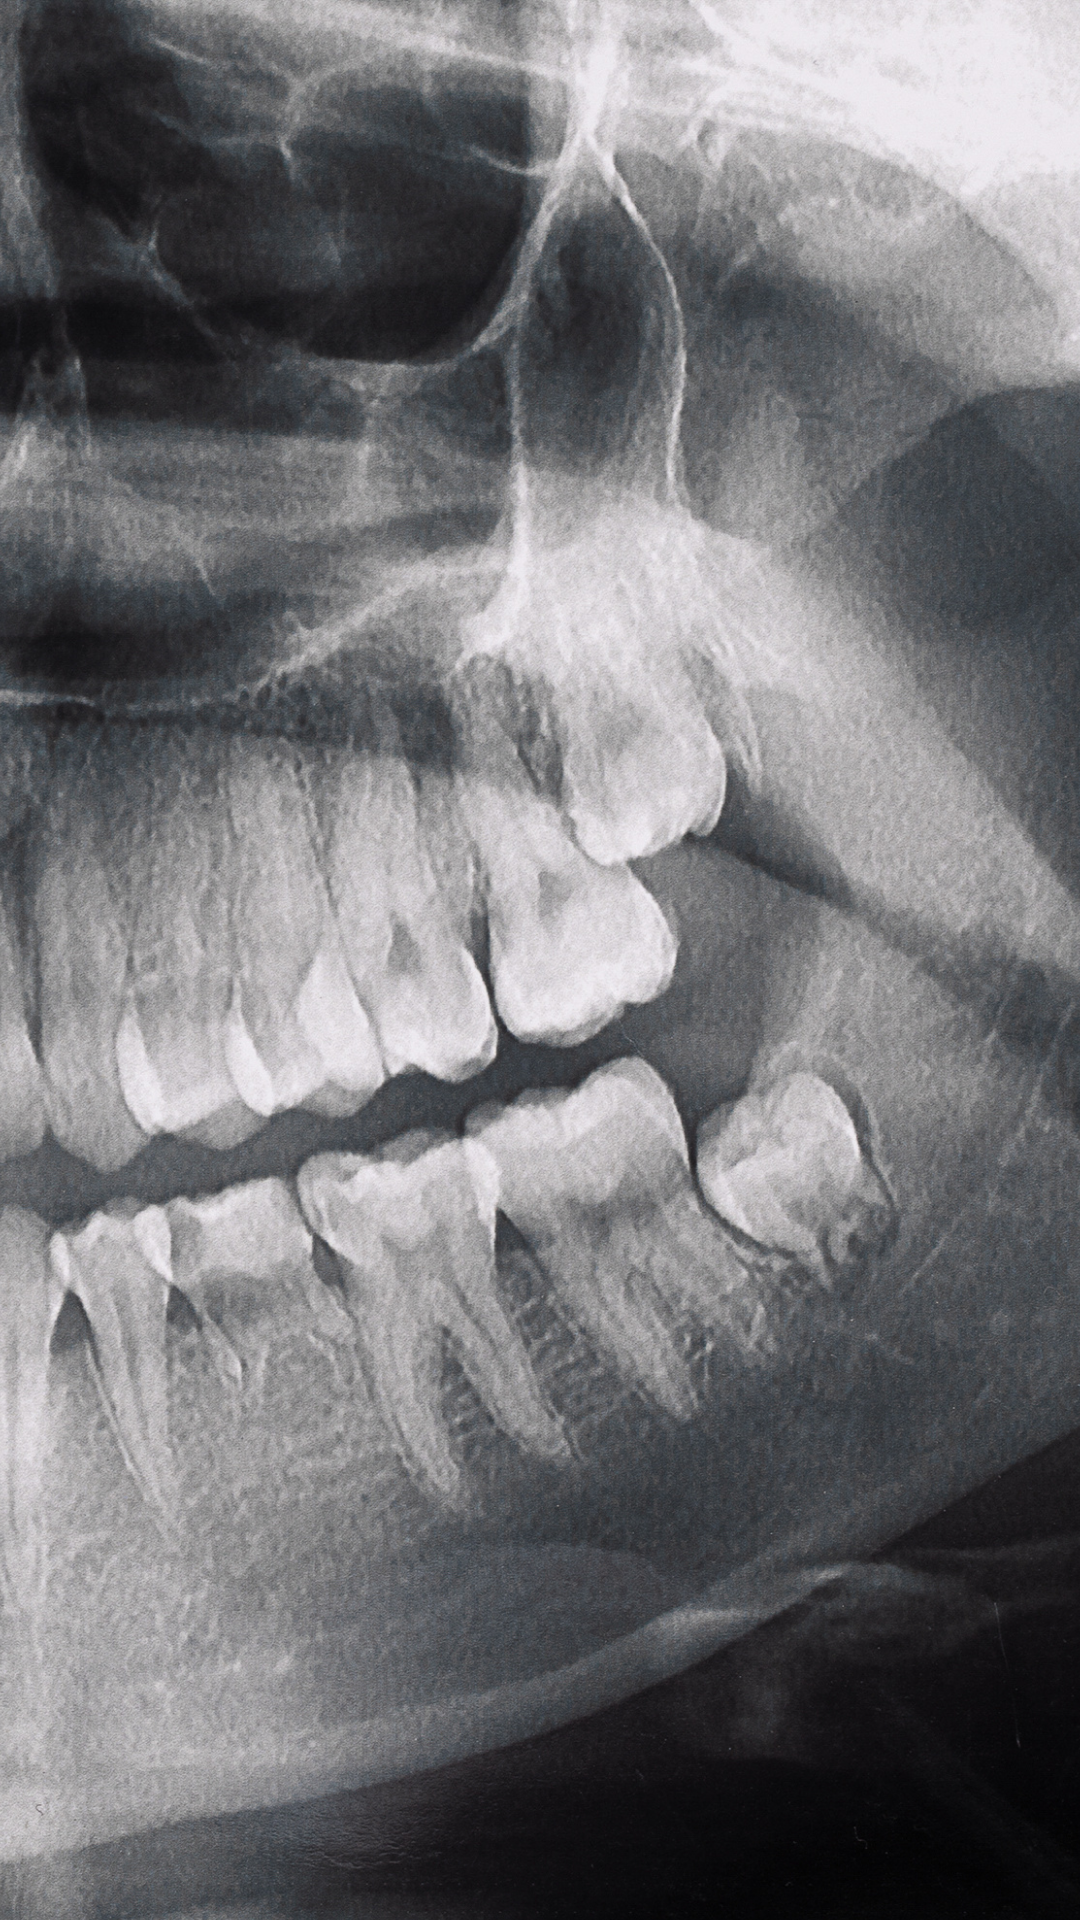

¿Necesitas imágenes tridimensionales precisas? Nuestras tomografías 3D te brindan diagnósticos milimétricos para planificación de tratamientos.

¿Necesitas estudios adicionales? Ofrecemos radiografías especializadas, reportes detallados y análisis de ATM para diagnósticos completos.